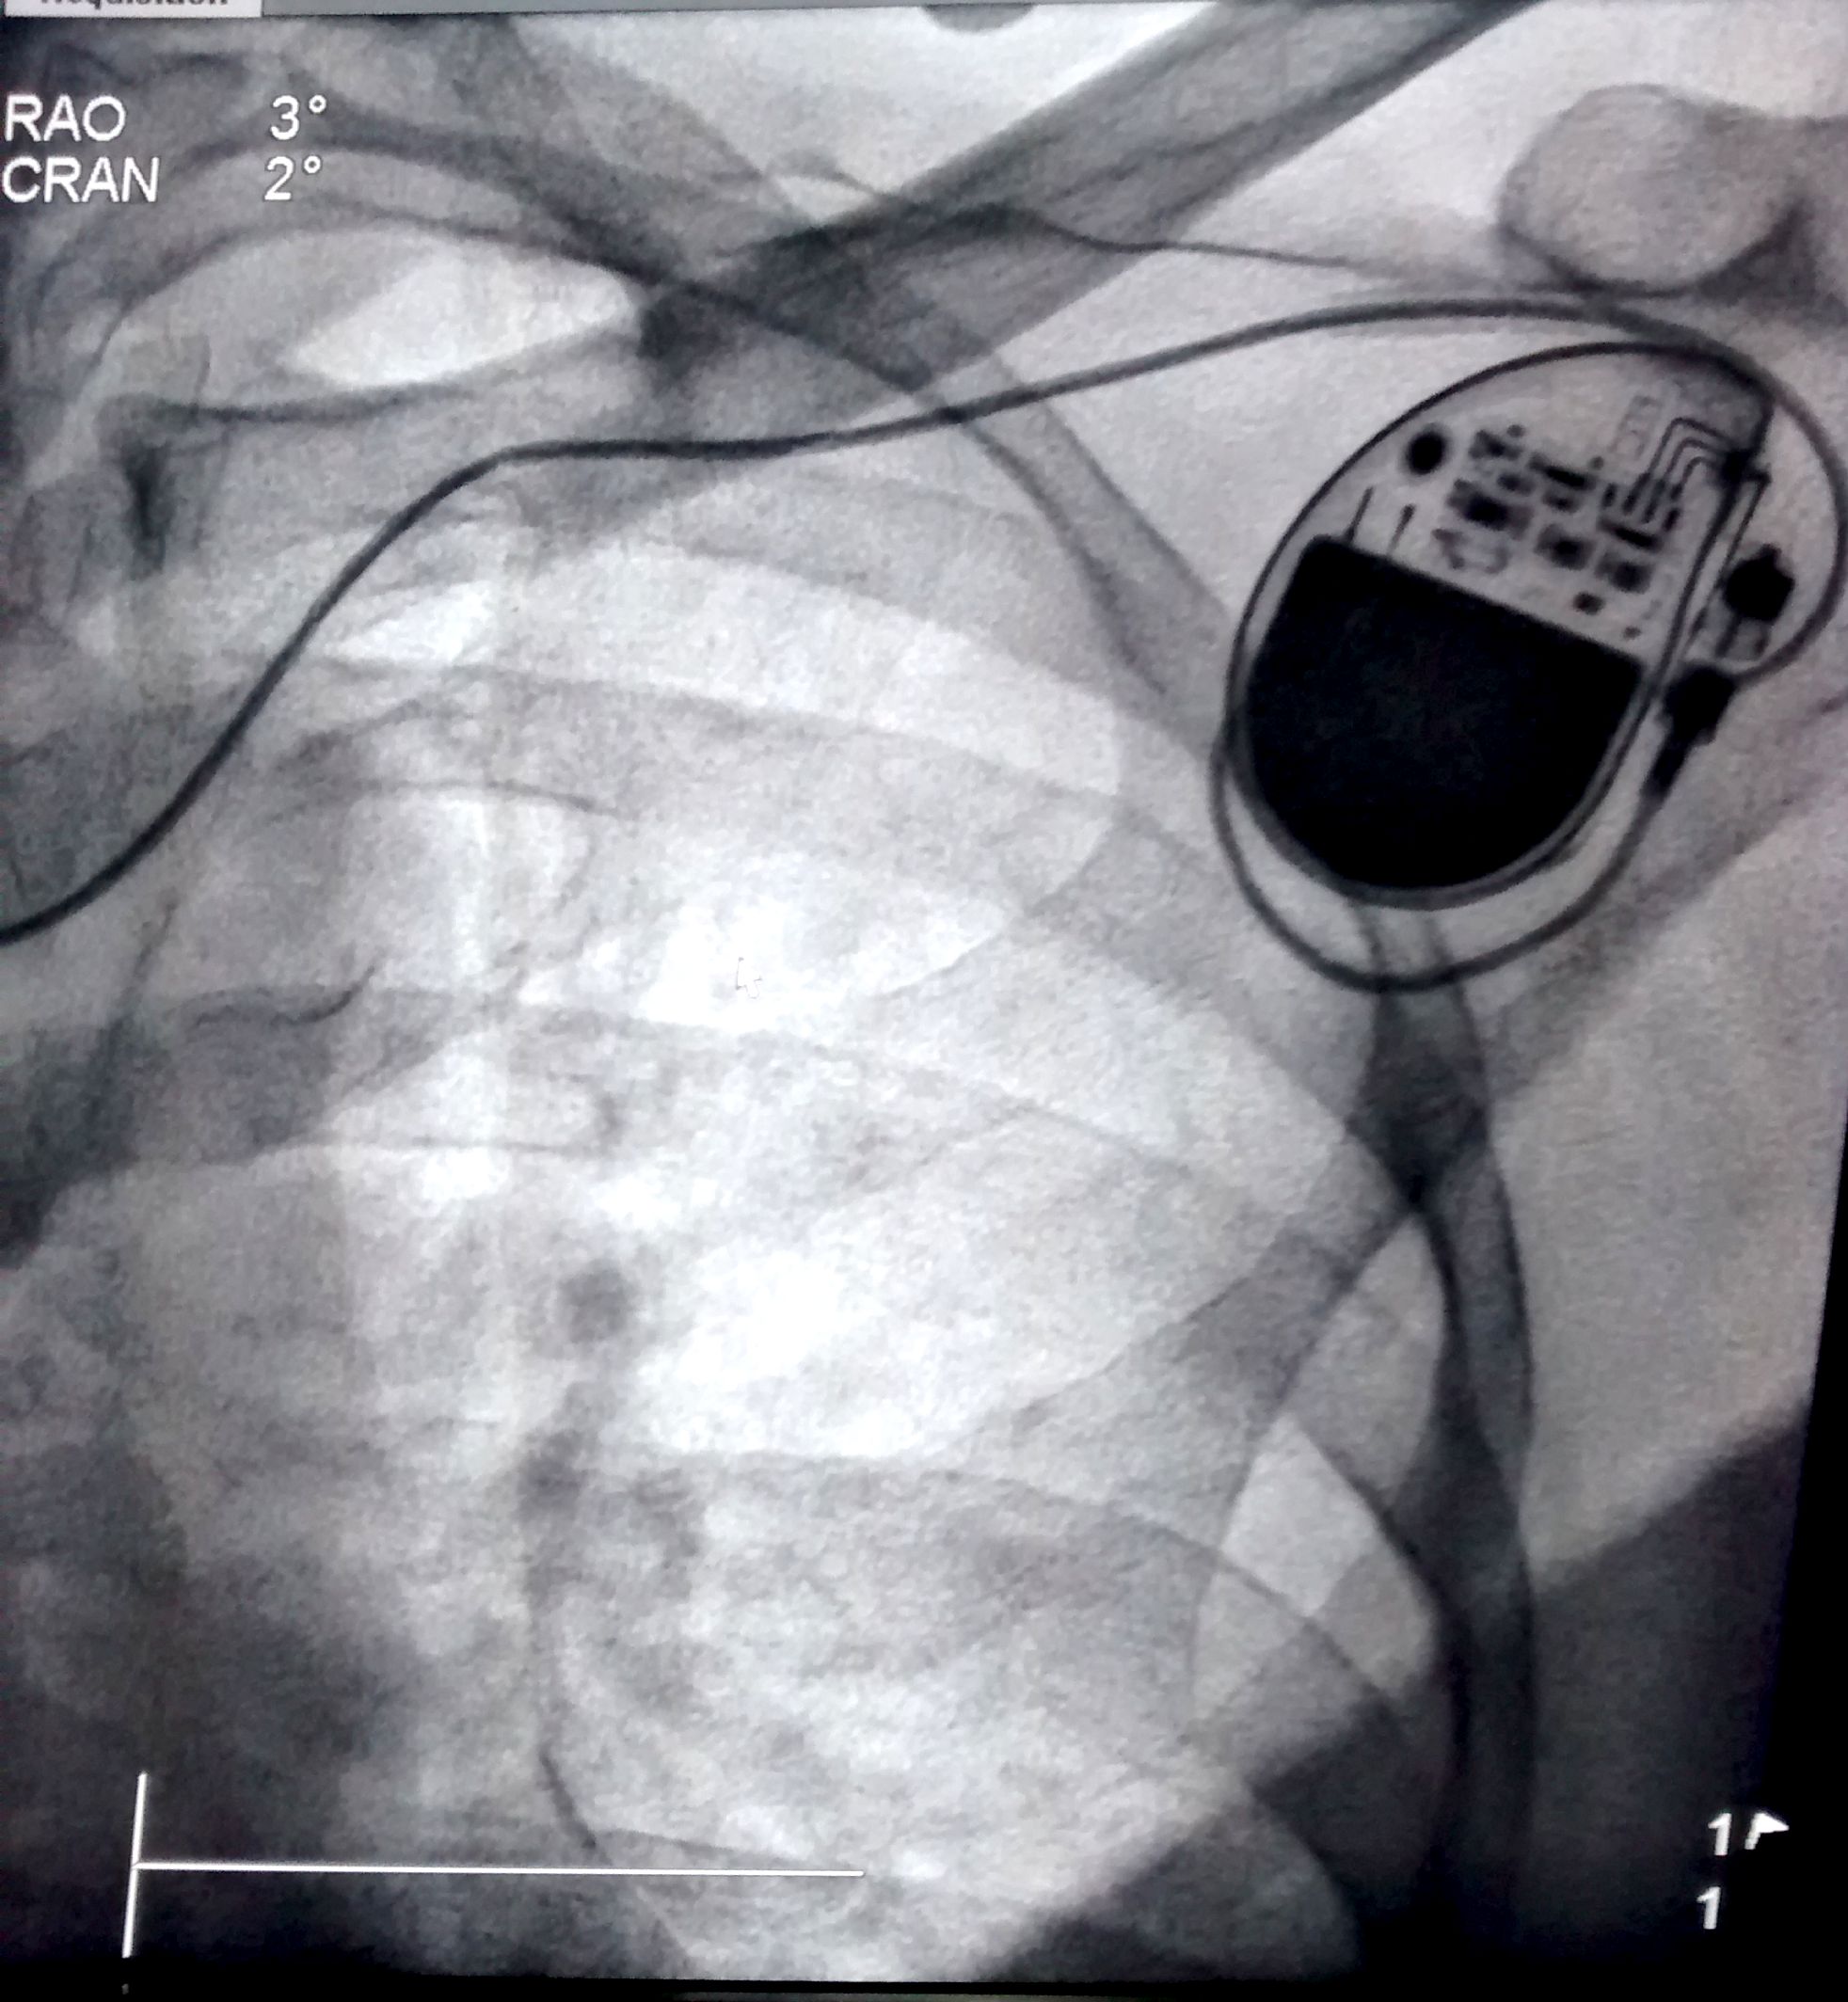

rvot_lead.jpg

RVOT pacing